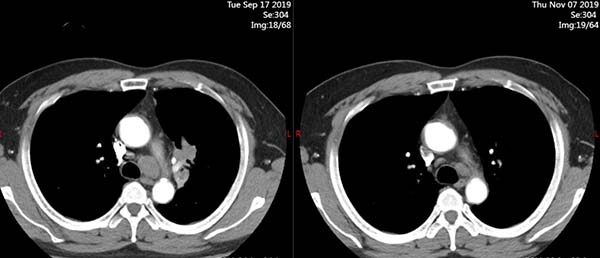

治疗前(2019.9.17)

治疗2周期后(2019.11.07)

在完成2个周期的治疗后,病灶显著缩小!时间是最好的试金石。一个月,两个月,一年,两年……至今,四年过去了。李某的病情得到了持续而深度的缓解,他定期返院复查,生活几乎恢复了正常。他可以重新陪伴孩子成长,可以陪着妻子散步,可以承担起家庭的责任。这四年,对他而言,是失而复得的黄金四年。